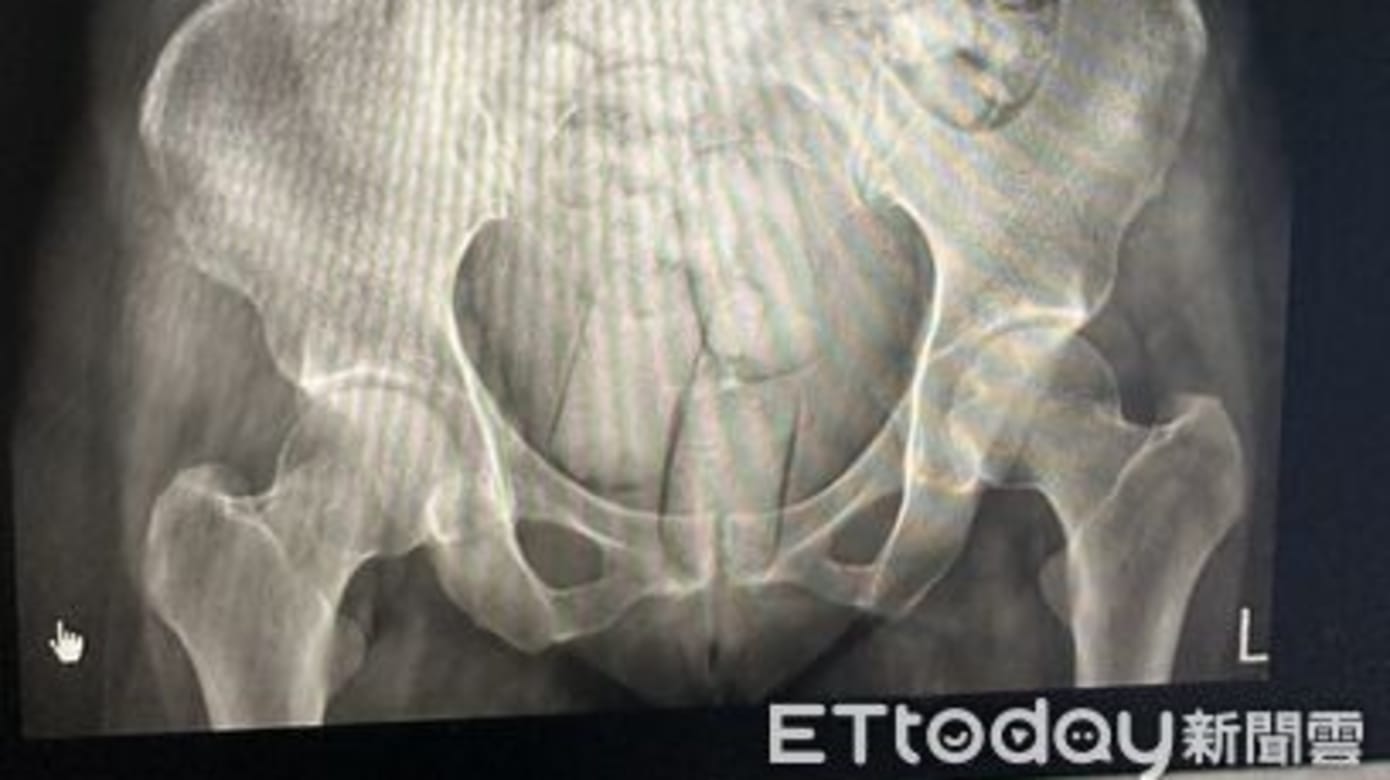

调查显示,两名女子事先在泰国将海洛因分装成可吞食的颗粒状以及可塞入肛门的长条状,并以防水薄膜及保险套双层包裹,防止胃酸融化毒品。

执法人员经翻译询问后,得知两人体内藏有大量毒品,立即将她们送往医院排出体内的毒品。

经统计,她们体内的毒品数量为664克,纯度约79%;其中一人排出54颗、重约390克的毒品,另一人则排出61颗、约273克的毒品。